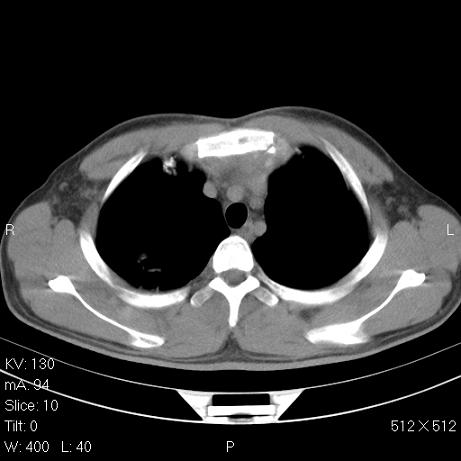

标题: CT7171B:补充治疗后2周复查

治疗后2周复查,请讨论

结合以前的ct片,还是考虑肺挫伤,吸收多了。

支持:创伤性湿肺。现肺挫裂伤(出血 积气)大部分吸收。建议继续治疗!

支持:创伤性湿肺、肺挫裂伤。现肺挫裂伤(出血、渗出、液气腔)大部分吸收。建议继续治疗!

经治疗后病灶明显吸收,考虑创伤性湿肺、肺挫裂伤